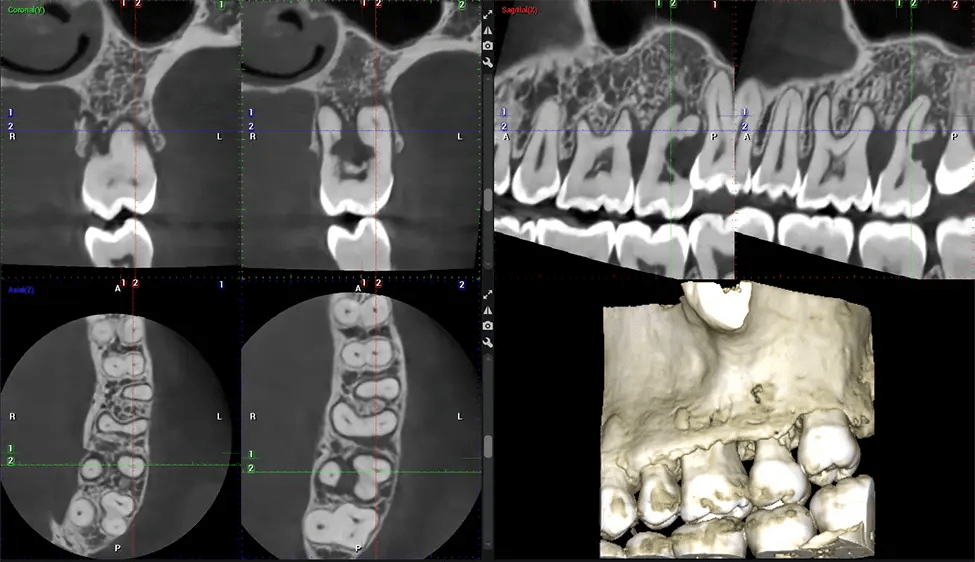

Esta exploración 3D, llamada tomografía computarizada de haz cónico, le brinda a su dentista una imagen más completa de su anatomía bucal y sus procesos patológicos que una radiografía tradicional. A diferencia de las radiografías convencionales, que capturan una imagen 2D de la boca desde varios ángulos, una exploración 3D toma varias radiografías digitales para una imagen. Proporciona una vista completa de la mandíbula, los dientes, los nervios y los tejidos blandos. Esta vista mejorada permite a los dentistas detectar problemas menores que no son visibles en las exploraciones 2D tradicionales, como muelas del juicio impactadas o fracturas óseas en la cavidad sinusal.

Otro beneficio importante es que las imágenes 3D proporcionan imágenes más precisas de la estructura ósea. Estas imágenes son más detalladas y le brindan un diagnóstico más preciso. Un diagnóstico preciso significa un mejor tratamiento para usted.

Nuestra tecnología SCARA patentada permite a los médicos capturar verdaderas alas de mordida extraorales que son tan precisas para detectar caries como una serie de alas de mordida 2D, pero con la mitad de la dosis de radiación. Con nuestras alas de mordida, los médicos pueden ver los ápices de los dientes en ambas mandíbulas, lo que proporciona una visión más completa de la anatomía de los pacientes.